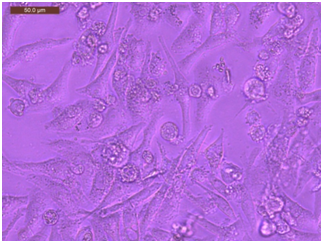

Propagation of the HEP-2 cell line: Human laryngeal squamous cell carcinoma (HEp2) cells were acquired from VACSERA® and grown in a sterile tissue 50cm2 flask in a complete medium that contained Dulbecco’s modified Eagle’s medium (DMEM), with a supplement of antibiotics (100U/ml penicillin and 100 μg/ml streptomycin) and 10% fetal bovine serum (FBS) in 95% air, 5% CO2 at 37°C (Figure 1). According to the time interval of 24, 48 and 72 hours, the cell line was propagated and subdivided into three separate groups.

Figure 1 Propagation of the HEP-2 cell line.